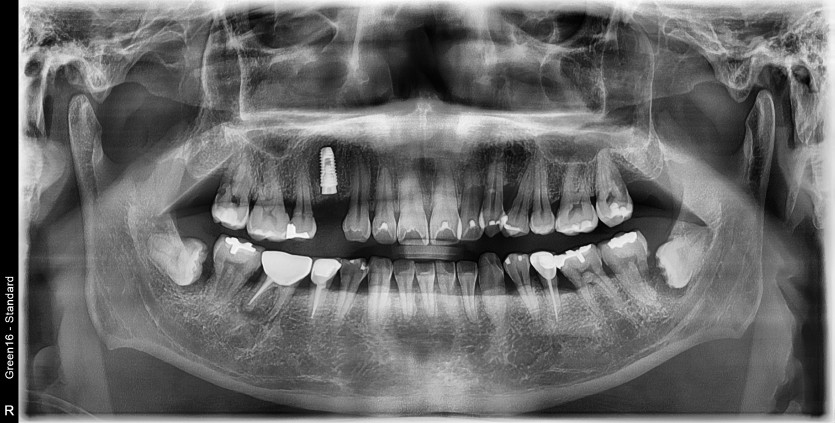

#38 사랑니 발치

구강외과 전문의가 발치했습니다.